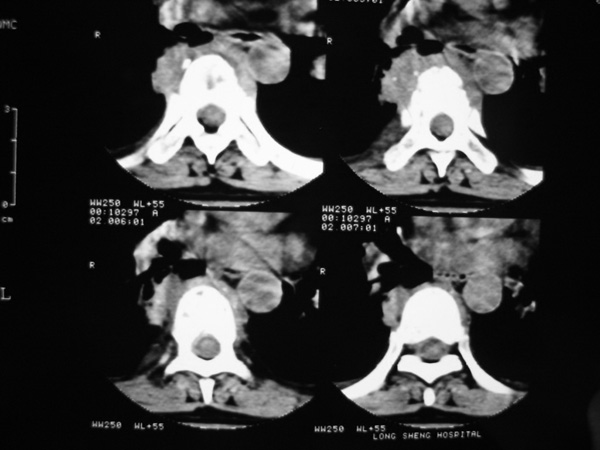

女,45岁,胸背部疼痛2个月。t6、7胸椎病变。

椎旁肿胀的软组织内可见气泡影,对脊柱的化脓性和结核性的鉴别有帮助吗?